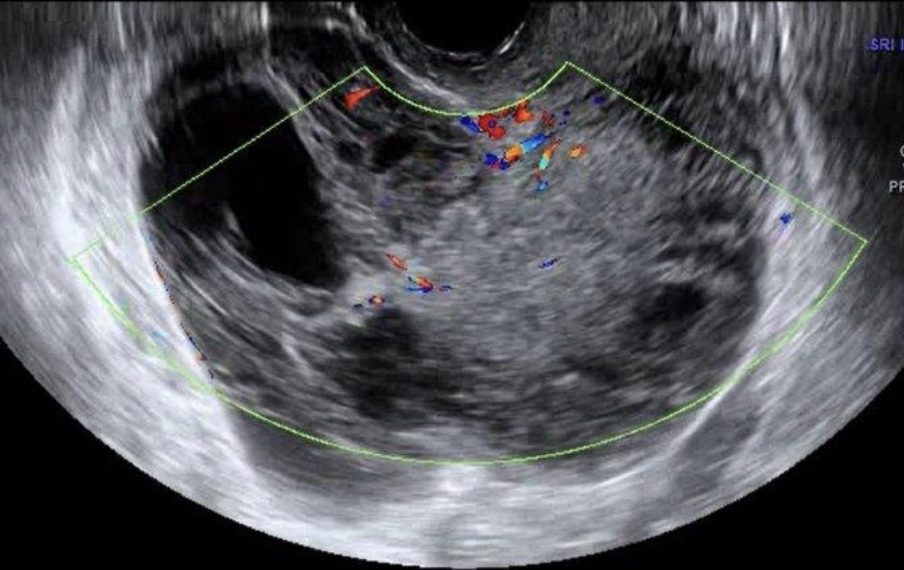

Casi del Mese di Febbraio 2022

Cari soci, finalmente le soluzioni dei casi del mese di Febbraio!

Caso 1

Caso 2